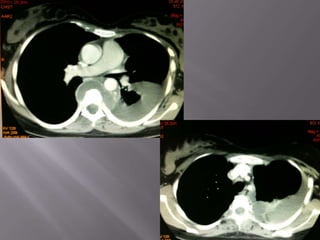

 Invasive thymoma in a young man. (A) Shows a lobular anterior

mediastinal mass associated with a pleural effusion. (B) Image

obtained through the lower chest demonstrates mixed soft tissue

(arrows) and fluid attenuation owing to transpleural spread.

 Invasive thymomain a young man. (A) Shows a lobular anterior mediastinal mass associated with a pleural effusion. (B) Image obtained through the lower chest demonstrates mixed soft tissue (arrows) and fluid attenuation owing to transpleural spread.